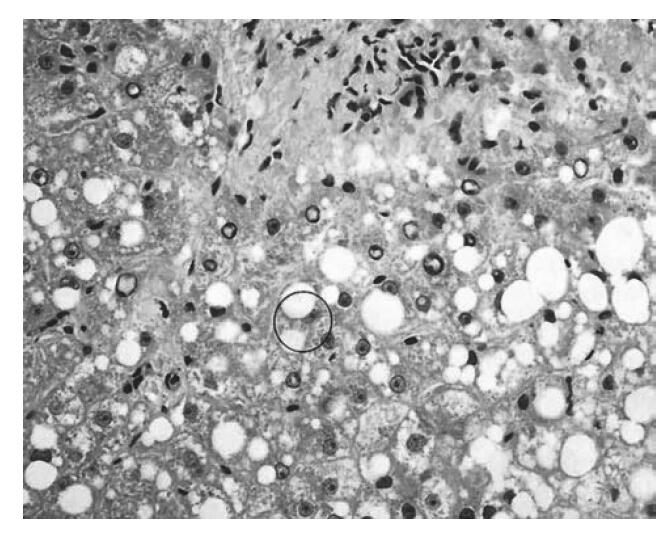

he×400 mallory小体

急性酒精性肝炎:mallory小体,肝细胞坏死,胶原沉积,脂肪变

酒精肝特有的病理损伤特点全部都有,气球样变,窦周纤维化,mallory小体

样变,可见脂肪样夹杂细胞肉芽肿,少数气球样变细胞,并见mallory小体

区轻度炎症,少量点灶状坏死,可见少数肝细胞气球样变,可见mallory小体